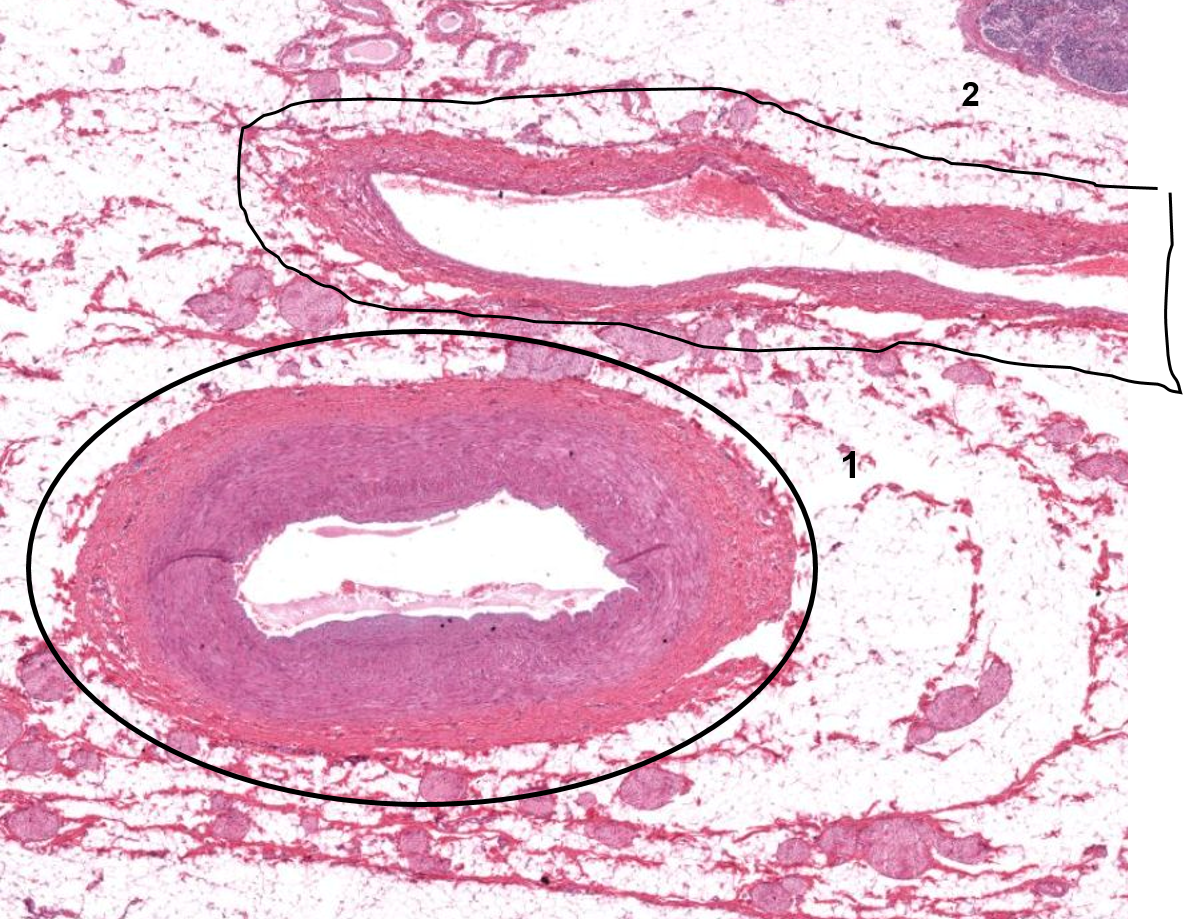

1: Artéria

2: Veia

1: Íntima

2: Média

3: Adventícia